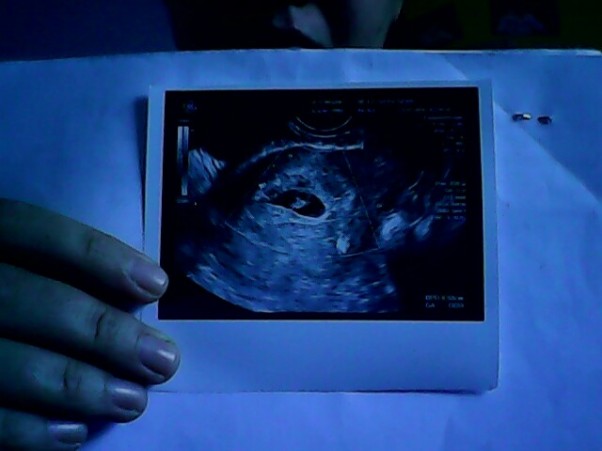

Nie milam internetu w szpitalu. W piatek lekarz powiedziala ze nie ma szans. Ze czeka tylko na moja prozbe. Modlilam sie, i plakalam, stracilam juz nadzieje. Mowilam ze mam tylko 1 % ktory zostawilam dla Boga, czas do soboty od srody ktory poswiecilam na modlitwe. W sobote z samego rana, doktor zrobil USG. CUD tylko tak moge nazwac to co zobaczylismy na ekranie. Malutkie serduszko. Malutkie lecz najwspanialsze serce ktore wkoncu zabilo dla mamy. Lekarz nie wierzyl.Trzy razy robil USG, jak zobaczyl maluszka zaniemowil.